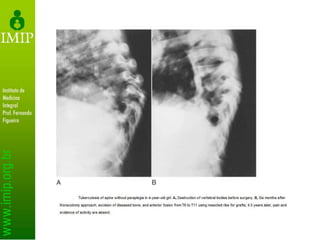

• Radiografia

– Alterações surgem entre 2 semanas e 3 meses

– Irregularidade da placa terminal

• erosões nas placas vertebrais são os primeiros achados

radiográficos

– Estreitamento do espaço discal

– Formação de osso hipertrófico (esclerótico)

– Achados tardios

• Colapso vertebral, cifose regional e anquilose óssea

– Tuberculose

• fina calcificação do tecido mole paravertebral

• Radiografias primárias

– Diminuição do espaço intervertebral

– Osteopenia localizada

• Radiografias tardias

– Colapso em sanfona (Seddon)

– Calcificação de partes moles